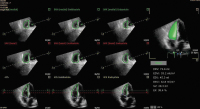

Abbildung 1: Standardschnitte bei der Untersuchung des rechten Herzens. Aus [Huber G, Glaser F. Echokardiographie des rechten Herzens. J Kardiol 2018; 25: 332–42]. RVOT: rechtsventrikulärer Ausflusstrakt; LVOT: linksventrikulärer Ausflusstrakt; MV: mitral valve; TI: Trikuspidalinsuffizienz; PA: Pulmonalarterie